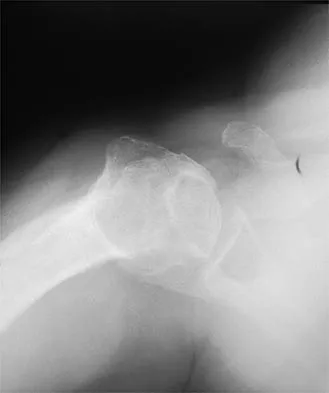

A paraplegic 32-year-old man was pulling himself up in bed by grasping the headboard rails when he felt a pop and immediate pain. A radiograph and CT scan are shown in Figures 2a and 2b. Based on these findings, management should consist of

Explanation

The coracoid process is an essential component of the superior shoulder suspensory complex and must be maintained. Open reduction and internal fixation is recommended if the fragment is large and displaced more than 1 cm. Froimson AI: Fracture of the coracoid process of the scapula. J Bone Joint Surg Am 1978;60:710-711.